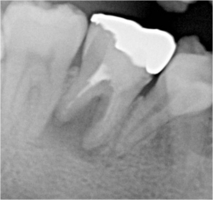

根管治療レッジ除去リカバリー症例

術前 ➡

術中

根の先に影(感染)が出てしまい根の治療を行わないといけないのですが以前他院にて処置を施した古い薬が入っています

画像を見ると手前の根にはしっかりと先まで薬が入っていません(1枚目の画像)

根のカーブに対応できず間違った方向へ削り込んでしまっています(赤矢印)

古い薬を除去しとあるテクニックを駆使し正しい根幹への道を見つけました(青矢印)

簡単にやっているように見えますがそのまま器具を入れては大きく間違った道に導かれてしまうなか、その脇から1mmにも満たない狭く曲がった孔を探しそちらへ導くのは至難の技ですが、マイクロスコープとCTを使いしっかりとした手法で行うとこのような症例にも対応できます